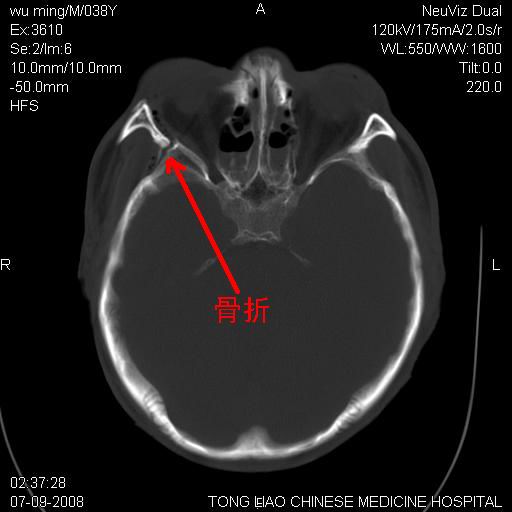

颅底多发骨折。

颅底多发骨折.

颅底多发骨折.上颌骨多发骨折

右侧眼眶,上颌骨,鼻骨、上颌窦等很多

骨折

颅底多发骨折!支持!

考虑:面骨、颅底骨多发骨折,颅内高压(脑肿胀)。

1)颅底骨及颌面骨多发性骨折。2)副鼻窦及双侧鼻腔积血。

多发性颅骨骨折

考虑:面骨、颅底骨多发骨折

前颅窝颅底骨折,死的原因应该从头部来看不用说就是重度颅脑损伤。

颅底、上颌骨,双侧颧骨多发骨折。死因或许与此无关,是否有腹部脏器损伤有关

考虑:面骨、颅底骨多发骨折。从五楼摔下还伤着头了,不死才怪;估计有弥漫性轴索损伤。